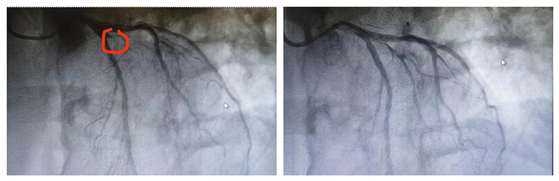

经心血管内科主任科彭道地、主任医师范爱德、副主任医师杨国栋、经治医师彭双等多名医生多次讨论后得出结论:根据患者冠脉造影结果,为分支血管堵塞,且对角支为小血管,若行支架植入术,可能影响前降支血流,建议行药物球囊扩张术。手术严格遵循PSP原则,顺利行药物球囊扩张术,手术过程顺利,没有出现并发症。

术前 术后